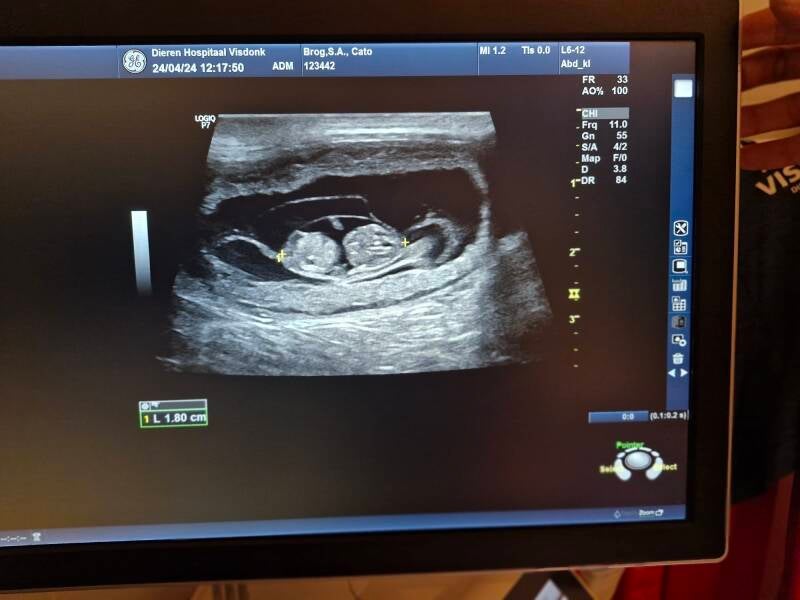

Dracht bevestigd!

Yeah! Catoo is drachtig! Sowieso zijn er 3 pups gezien, heeeel misschien een 4de al verwachten we die niet.